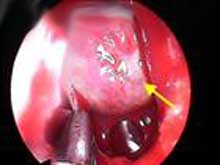

3.手術治療 微腺瘤,可經蝶竇手術治療,腺瘤超過10mm如有下述指征需經顱手術

(1)手術指征:①腫瘤向鞍上生長視神經交叉受壓下丘腦及第三腦室受壓引起腦積水等症狀者;②腫瘤向鞍前生長達到前顱凹額底者;③垂體卒中;④放射治療效果不滿意或惡化者;⑤有功能性或無功能性腺瘤產生臨床垂體功能亢進或減退者